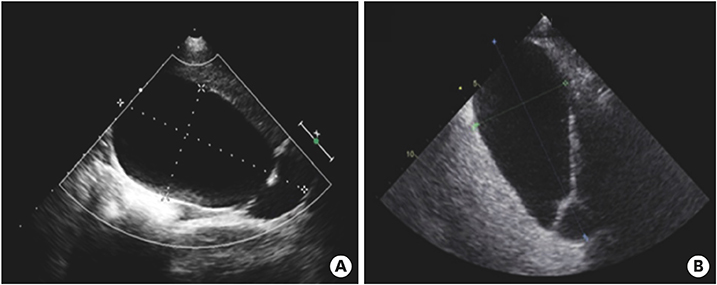

On the first day after admission, he received 2 g/kg IVIG and 50 mg/kg/day aspirin, following which his fever subsided and no further IVIG treatment was needed. His first echocardiography showed myocarditis (ejection fraction [EF], 45%) and mild ectasia of left main coronary artery (3.2–3.4 mm in diameter). On the second day after his admission, echocardiography (second follow-up) showed improved mild myocarditis (EF, 55%), improved ectasia of left main coronary artery (2.7–2.8 mm in diameter), and severe GB distension (8.9×4.6 cm in size), which possibly indicated GB hydrops (Fig. 2A). On the fourth day after his admission, although he had no fever and exhibited improvements in KD symptoms (i.e., eye injection, rash on abdomen, and cervical lymphadenopathy), he still complained of abdominal pain, distension, and tenderness of the RUQ. Follow-up laboratory findings were improved: neutrophilic leukocytosis (6,130 cells/mm3, with 33% neutrophils); decreased CRP (4.4 mg/dL), BNP (347 pg/mL), AST (40 U/L), and ALT (72 U/L); and improved hyperbilirubinemia (total bilirubin, 0.7 mg/dL). Echocardiography (third follow-up) showed normal completely improved carditis and still severe GB distension (10.2×5.5 cm in size) (Fig. 2B). Abdominal ultrasonography (US) was performed, which showed a markedly distended GB without stone, sludge, or wall thickening as well as normal bile ducts and liver morphology, which confirmed GB hydrops (Fig. 3A). On the sixth day after his admission, although his signs of KD had nearly disappeared, he still complained of abdominal discomfort, which had been moderately improving. The second follow-up abdominal US revealed a no notable change in GB distension compared to previous sonographic findings (Fig. 3B). An abdominal computed tomography (CT) scan was also obtained to exclude other hepatobiliary abnormalities, which showed similar findings as sonography, including a marked dilatation of the GB (8.0×5.5 cm in size) without stone, sludge, or wall thickening as well as normal bile ducts and liver morphology (Fig. 4). No complications necessitating surgical intervention had occurred and he was discharged 7 days after admission with only mild tenderness on the right upper-mid quadrant.

Fig. 2

Echocardiography showed severe gallbladder distension (A) 8.9×4.6 cm in size and (B) 10.2×5.5 cm in size.

After discharge and 23 days of fever onset, a follow-up abdominal sonography revealed a slower regression of the GB hydrops (Fig. 5A). Echocardiography performed at 81 days after onset of fever revealed complete improvement of both the coronary artery lesion and GB hydrops (Fig. 5B).

Fig. 5

Abdominal ultrasonography (A) performed at 23 days after fever onset revealed a slow regression of the gallbladder hydrops (6.7×3.2 cm in size). Echocardiography (B) performed at 81 days after fever onset revealed a complete improvement in gallbladder hydrops and a normal gallbladder.